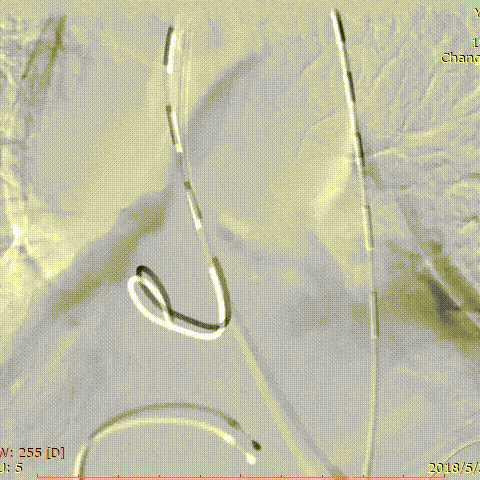

在国际上,多项临床试验正在积极推进。Gore公司资助的ARISE系列研究(ARISE I、II、III)进展顺利。其中,ARISE研究评估GORE® Ascending Stent Graft在DeBakey I/II型主动脉夹层治疗中的应用。

这款专用支架的特点包括:

更大口径:34mm-53mm

三个长度尺寸:7cm、8cm、10cm

精确释放设计:分步释放,成角控制

避免冠脉覆盖:sleeve pullback机制、近端小裸段设计。

ARISE I已完成43例入组,ARISE II于2023年12月完成招募,入组标准已从慢性夹层扩展至急性夹层。